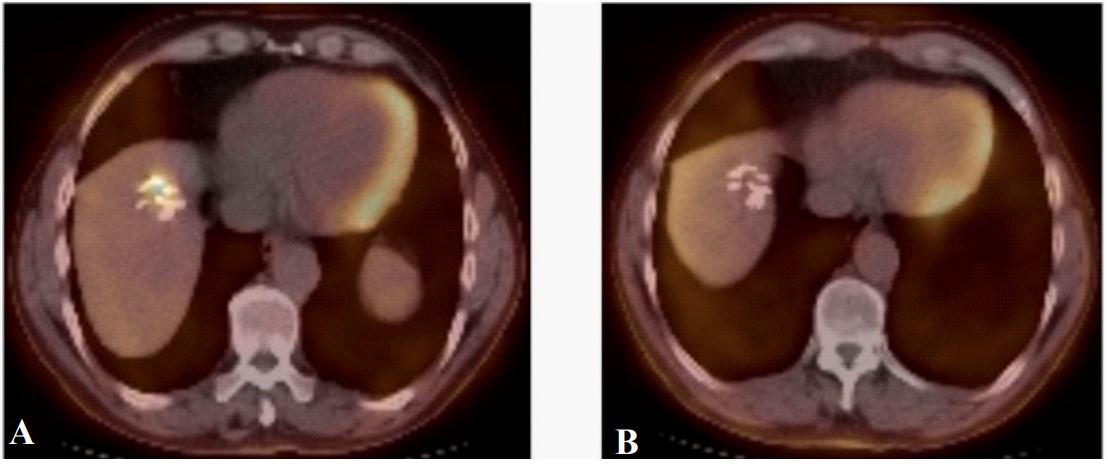

Nine months after liver resection, CT-imaging revealed an increase in the size of left para-aortic lymph nodes, while PET-CT confirmed pathologic para-aortic lymph node disease and hypermetabolism at the resection site in segment VII (SUV 4,9) (Figure 4).

After a second line induction chemotherapy, surgical exploration with intraoperative liver ultrasound was performed, with resection of a segment VII, and extended lymphadenectomy. Pathology of segment VII found a necrotic lesion, containing staples, surrounded by fibro-inflammatory tissues and granulomas, while lymphadenectomy specimens confirmed metastatic disease.

Figure 4: Representative images of PET-CT metabolic activity in the site of previous wedge resection on segment VII (SUV 4,9)